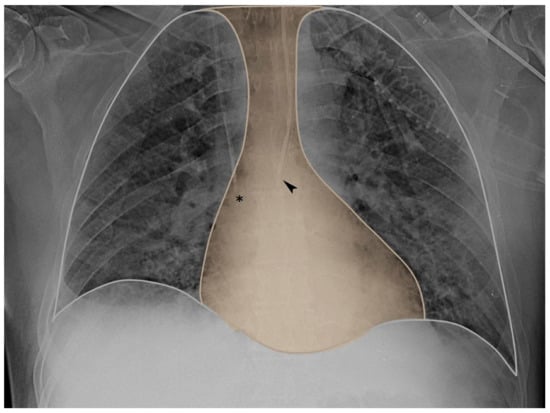

In particular, positive pressure mechanical inspiration increases intrathoracic pressure, thus causing a positive ΔCVP that reduces venous return. Conversely, spontaneous inspiration decreases intrathoracic pressure, thus causing a negative ΔCVP that increases venous return [30]. Indeed, this increase in venous return is limited; when the pressure drops below atmospheric pressure, the great veins collapse and develop a flow limitation. Therefore, based on these physiological assumptions, CVP appears to have respiratory oscillations that reflect intrathoracic (i.e., pleural) pressure changes. The extent of the respiratory swing in CVP was shown to be of a similar extent to that of Pes, which is also justified by the close anatomical position of the two measurement systems (as depicted in Figure 1 and Figure 2, upper panel).

Figure 1. Chest X-ray mediastinum view. The tip of the central venous catheter (asterisk) and the tip of the esophageal balloon (arrow) are both closely located within the mediastinum (yellow area).